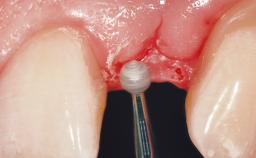

Late Placement of an Implant in a Maxillary Left Central Incisor Site

A 36-year-old female patient was referred for the replacement of the upper left central incisor (tooth 21), which had fractured. Although the tooth had been asymptomatic for many years, the crown began to loosen, at which time she presented to her dentist for an assessment. Teeth 21 and 22 had both been endodontically treated many years previously. She was a healthy individual and a non-smoker.

Soft Tissue Grafting Simultaneous